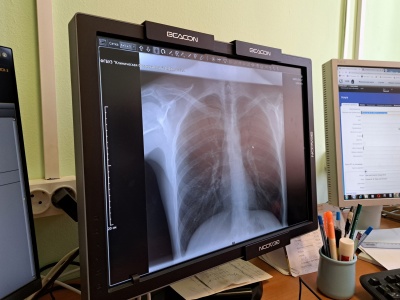

В КБ-50 закуплен цифровой рентген вместо плёночного

Недавно в распоряжение КБ-50 поступил современный цифровой рентгенодиагностический комплекс на три рабочих места. «Он позволяет проводить рентгенографию и рентгеноскопию. Мы можем диагностировать заболевания органов грудной клетки и брюшной полости, суставов, костей, позвоночника. Сама процедура проходит намного быстрее, чем на старом, пленочном оборудовании и занимает в среднем 5 минут, что удобно как для лаборанта, так и для врача. Если раньше мы делали снимок, затем его проявляли и только потом приступали к описанию, то сейчас вся информация сразу передается на компьютер», — рассказал врач-рентгенолог Иван Грушин.

«Снимки получаются очень высокого качества. Я могу подстроить под себя яркость и контрастность, рассмотреть мелкие детали. Аппарат оснащен современным программным обеспечением, которое помогает быстро и точно проводить диагностику, вести протоколы исследований. Снимки сохраняются в электронном виде в информационной системе и врач, который направил к нам пациента, может сразу увидеть результаты. При необходимости есть возможность записать их на диск», — рассказал врач-рентгенолог Иван Грушин.